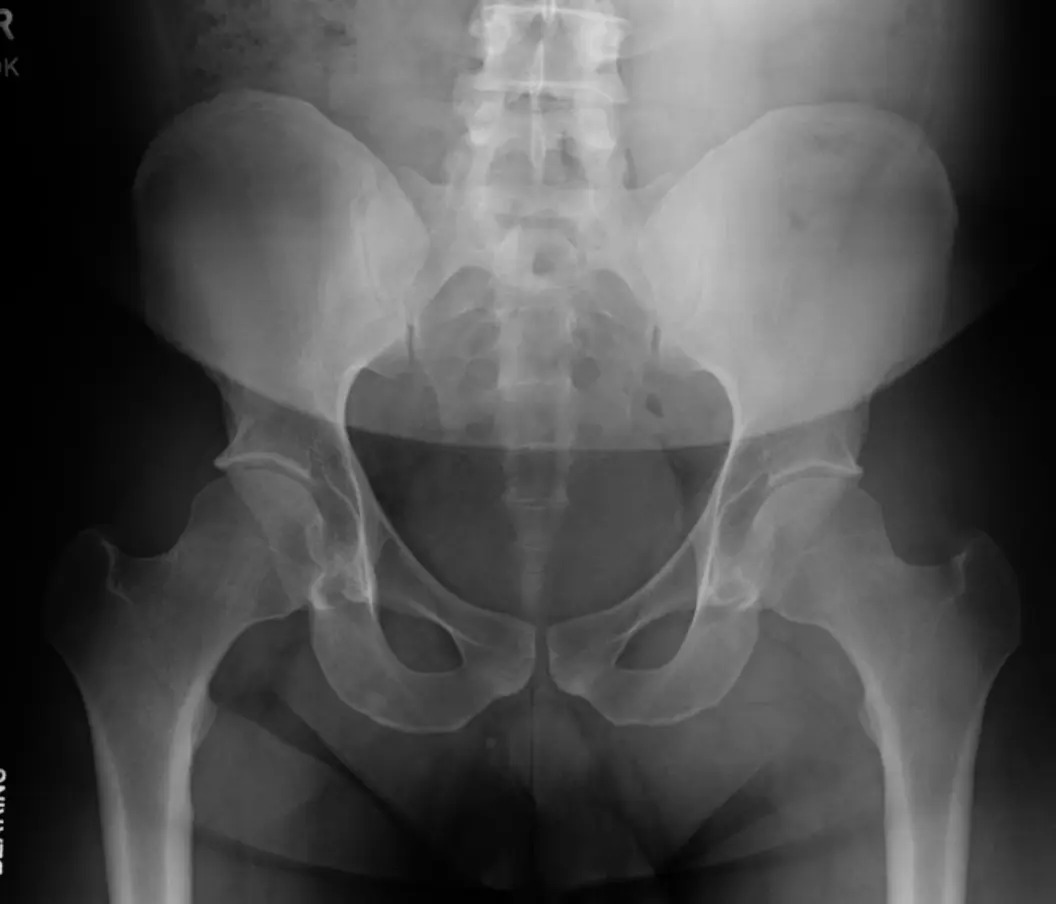

- Pelvic X-ray

Anteroposterior chest X-ray showing a suggestive pulmonary nodule/mass.